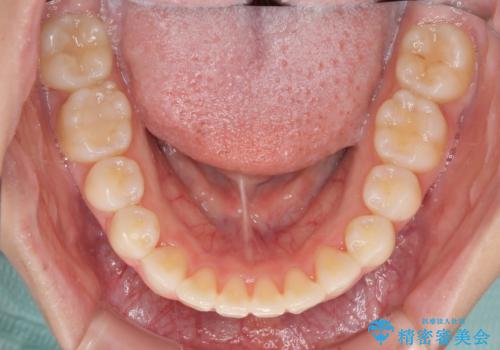

毎日しっかりと装着してくださったので、概ねシミュレーション通りに歯を移動させることができました。

治療前には接触することのなかった上下の前歯が接触するようになり、食事の際前歯でものをかみ切れるようになりました。

気にしていた口元の印象が改善され、患者様には大変満足していただきました。